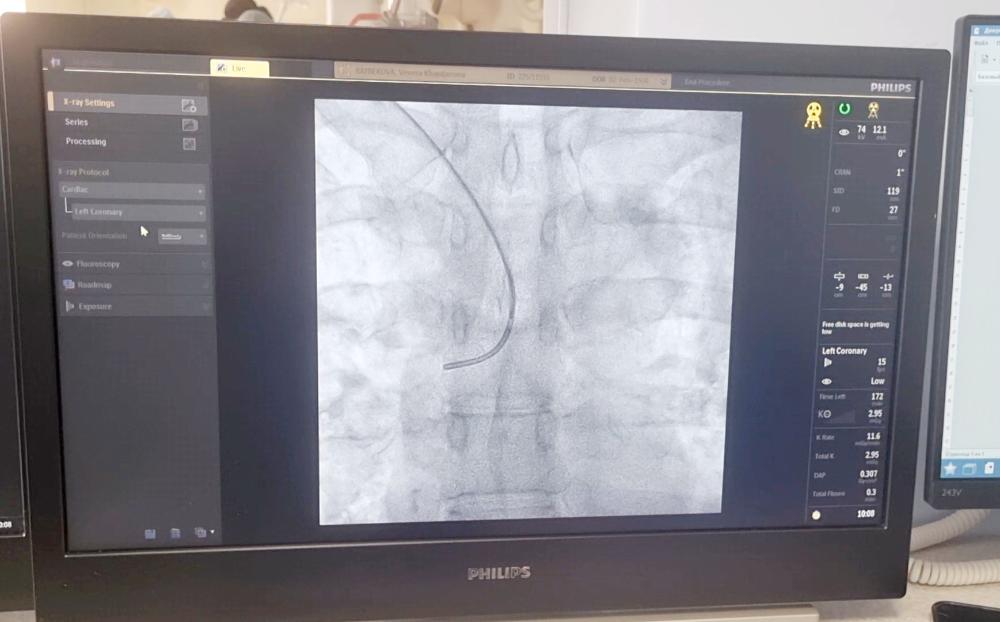

На базе регионального сосудистого центра больницы селективную химиоэмболизацию сосудов изучили пензенские врачи-онкологи и врачи–рентгенохирурги.

Особенностями применения технологии с пензенскими коллегами поделился к.м.н., врач по рентгенэндоваскулярным методам диагностики и лечению, врач-онколог МРНЦ им А.Ф. Цыба - филиала НМИЦ радиологии Минздрава России Фёдор Трифонов.

«Эмболизация – это вид эндоваскулярной хирургии, при котором происходит блокирование сосуда при помощи специального специальных эмболизационных препаратов, - пояснил Фёдор Александрович. - Эмболизация отличается наименьшим риском для пациента и временем восстановления».

В рамках мастер-класса во вторник, 3 июня, в больнице проведены три операции пациентам, у которых имелись образования разных локализаций.

«Под контролем ангиографа при помощи химиопрепарата произведена химиоинфузия, которая позволяет закрыть сосуд, чтобы опухоль перестала питаться, - уточнил главный врач Областного онкологического клинического диспансера, также изучающий данную технологию в рамках мастер-класса. - В результате образование уменьшается в размерах».